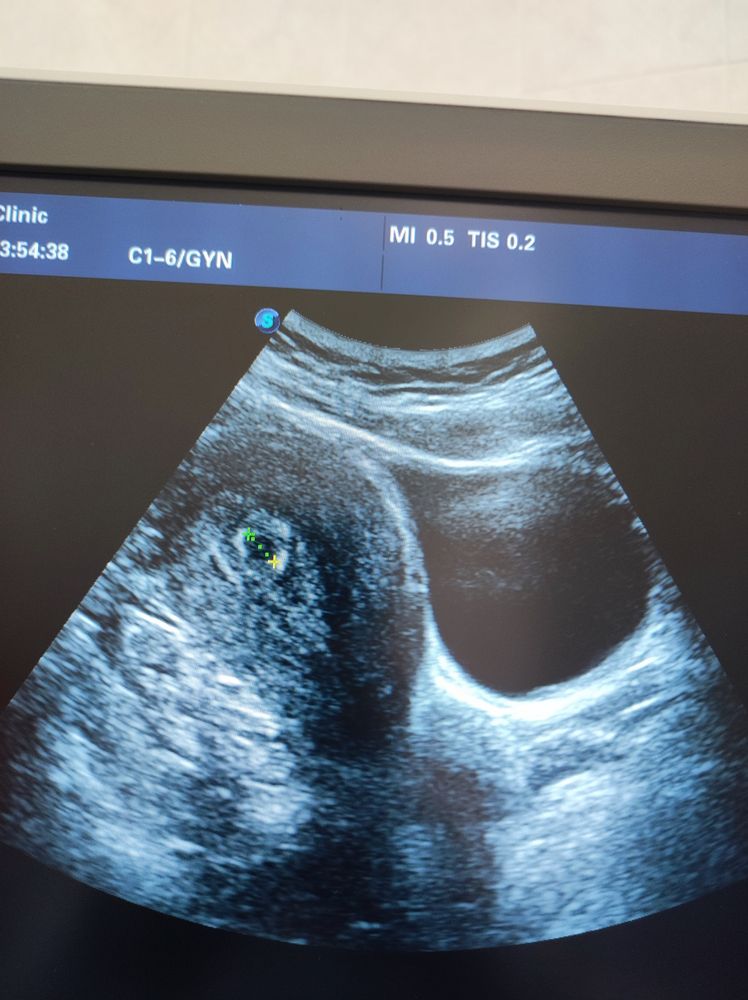

У нас получилось! Я беременна!Беременность акушерские 5 недель и 3 дня .с самого начала были боли в животе ,тянуло яичник ..очень переживала что внематочная,так как 7 лет назад столкнулась с этим ..вчера сходила на УЗИ ,меня успокоили ...для моего срока все отлично )правда сердечко ещё не услышала ,но уверенна оно бьётся